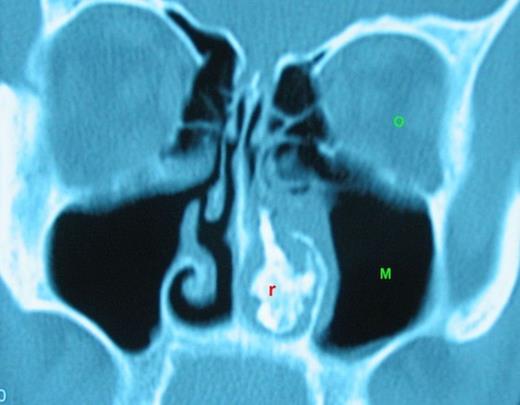

A computed tomography (CT) was performed and a left sided mass in the inferior meatus which has demonstrated central calcification was reported (Figure 1). Mild mucosal hypertrophy was present in the left ethmoid and maxillary sinuses, accompanied with ipsilateral asymmetric adenoid hypertrophy (Figure 2).

Rinolith is seen on the left nasal cavity. (r: rinolith, O: orbit, M: Maxillary sinus)